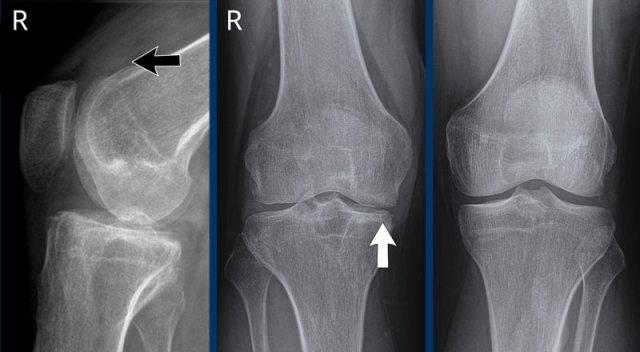

Hình ảnh cho thấy các hạt tophi lan rộng quanh khớp gối ở bệnh nhân gout (đầu mũi tên).

Tại khớp gối, các vị trí này (điểm bám gân khoeo, điểm bám gân tứ đầu đùi, điểm bám dây chằng bên trong – MCL) rất điển hình.

Có tràn dịch khớp mức độ nhẹ.

Hẹp khe khớp có thể do thoái hóa khớp thứ phát.

Giãn túi cùng trên xương bánh chè của khớp gối phải do tràn máu khớp (mũi tên đen).

Hẹp khe khớp phía trong do phá hủy sụn và viêm khớp thoái hóa thứ phát (mũi tên trắng).

Hình thành nang xương dưới sụn phía dưới gai liên lồi cầu.

Không có hình ảnh bào mòn xương.